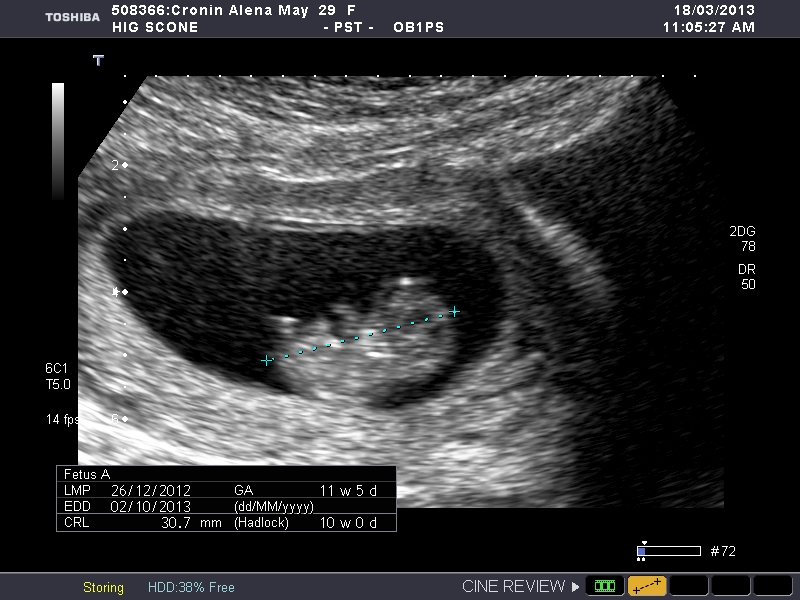

So maybe to early I had a date scan yesterday 10.2 weeks and I read on the net that for nub theory you have to be 10-14 weeks so I thought I would post here so we can guess. My next scan is at 13 weeks so I will post them to and I can compair. So what do you think boy or girl? I am desperate to know.

Attachment 9734

Attachment 9735